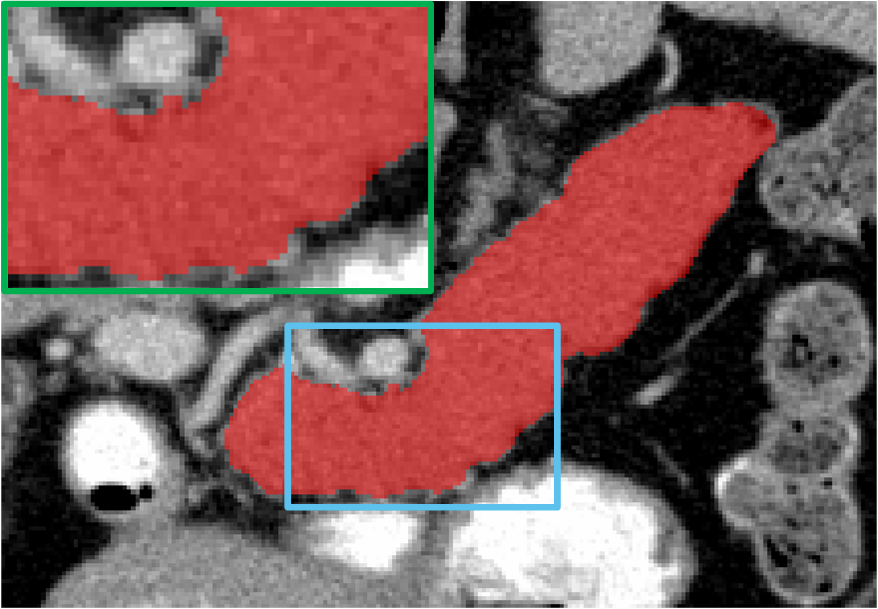

4.4 Result on Pancreas-CT Dataset

Table 2 shows the results specific to Pancreas-CT. Note that the volumes in this dataset provide a more complex backdrop compared to LA MRIs, rendering pancreas segmentation a more challenging task. To facilitate an intuitive comparison, we again employ several state-of-the-art competitors, namely UA-MT [42], SASSNet [17], DTC [20], MC-Net+ [37], RCPS [45], and CauSSL [22]. The performance metrics reported in their respective papers are directly adopted. Similarly, we employ Vnet with varying proportions of labeled data (10%, and 20%) for comparative analysis. Similarly, we select 6 samples for 10% supervision and 12 samples for 20% supervision from the training dataset, and consider the remainder as unlabeled data.

Yet within a notably challenging task, the proposed DCF demonstrates promising performance in both scenarios. Even with only 10% of the data labeled, DCF significantly improves Dice scores from 55.10% to 78.94%, surpassing all other SSL methods. With 20% labeled data, DCF achieves a Dice score of 81.65%, outperforming again other cutting-edge competitors. It should be noted that our proposal exhibits the smallest disparity between 10% and 20% labeled scenarios, as illustrated in Figure 4. The marginal 2.71% variance in DCF’s Dice scores between these proportions suggests its effective utilization of unlabeled data, thereby demonstrating robustness and generalization capabilities. We further deliver visualization of the results obtained by DCF and others, as illustrated in Figure 6. It is observed that our results closely resemble the ground truth (GT) compared to those of other methods. Moreover, our method exhibits more precise boundary positioning and provides the more detailed information.